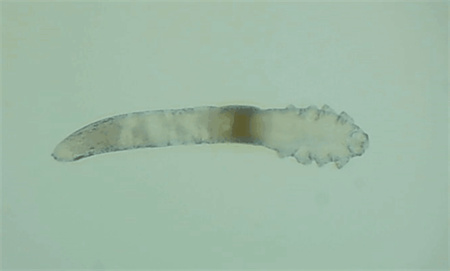

5、螨蟲檢查

從每只眼上(眼瞼)拔3根睫毛,在顯微鏡下觀察是否存在蠕形螨,以及數(shù)量多少。

如果任意一個(gè)眼瞼螨蟲數(shù)量≥3只,就需要除螨治療了。眼瞼螨蟲過多會(huì)造成機(jī)械性損傷,附帶細(xì)菌還會(huì)引起瞼緣感染,后續(xù)會(huì)有干癢、紅腫、分泌物增多、睫毛脫落等一系列問題。